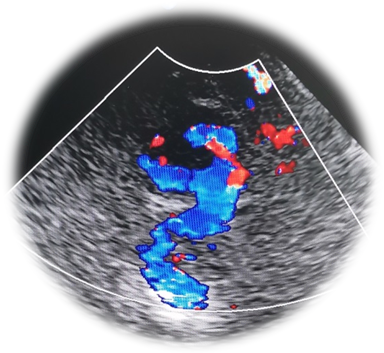

TCCD在TCD成像基础上,加入二维灰阶成像及彩色多普勒血流成像可直观地识别颅内结构,尤其可以观察帕金森病黑质有无高回声及其范围,第三脑室及侧脑室前角的宽度、中脑、丘脑结构、脑内重要核团如中缝核、红核回声,更准确的定位颅内血管,通过角度校正,可更为准确地取得狭窄处,狭窄前、狭窄后血管腔的实时血流动力学信息。定位及定性更加准确、全面,对侧枝循环的评估更加精确。